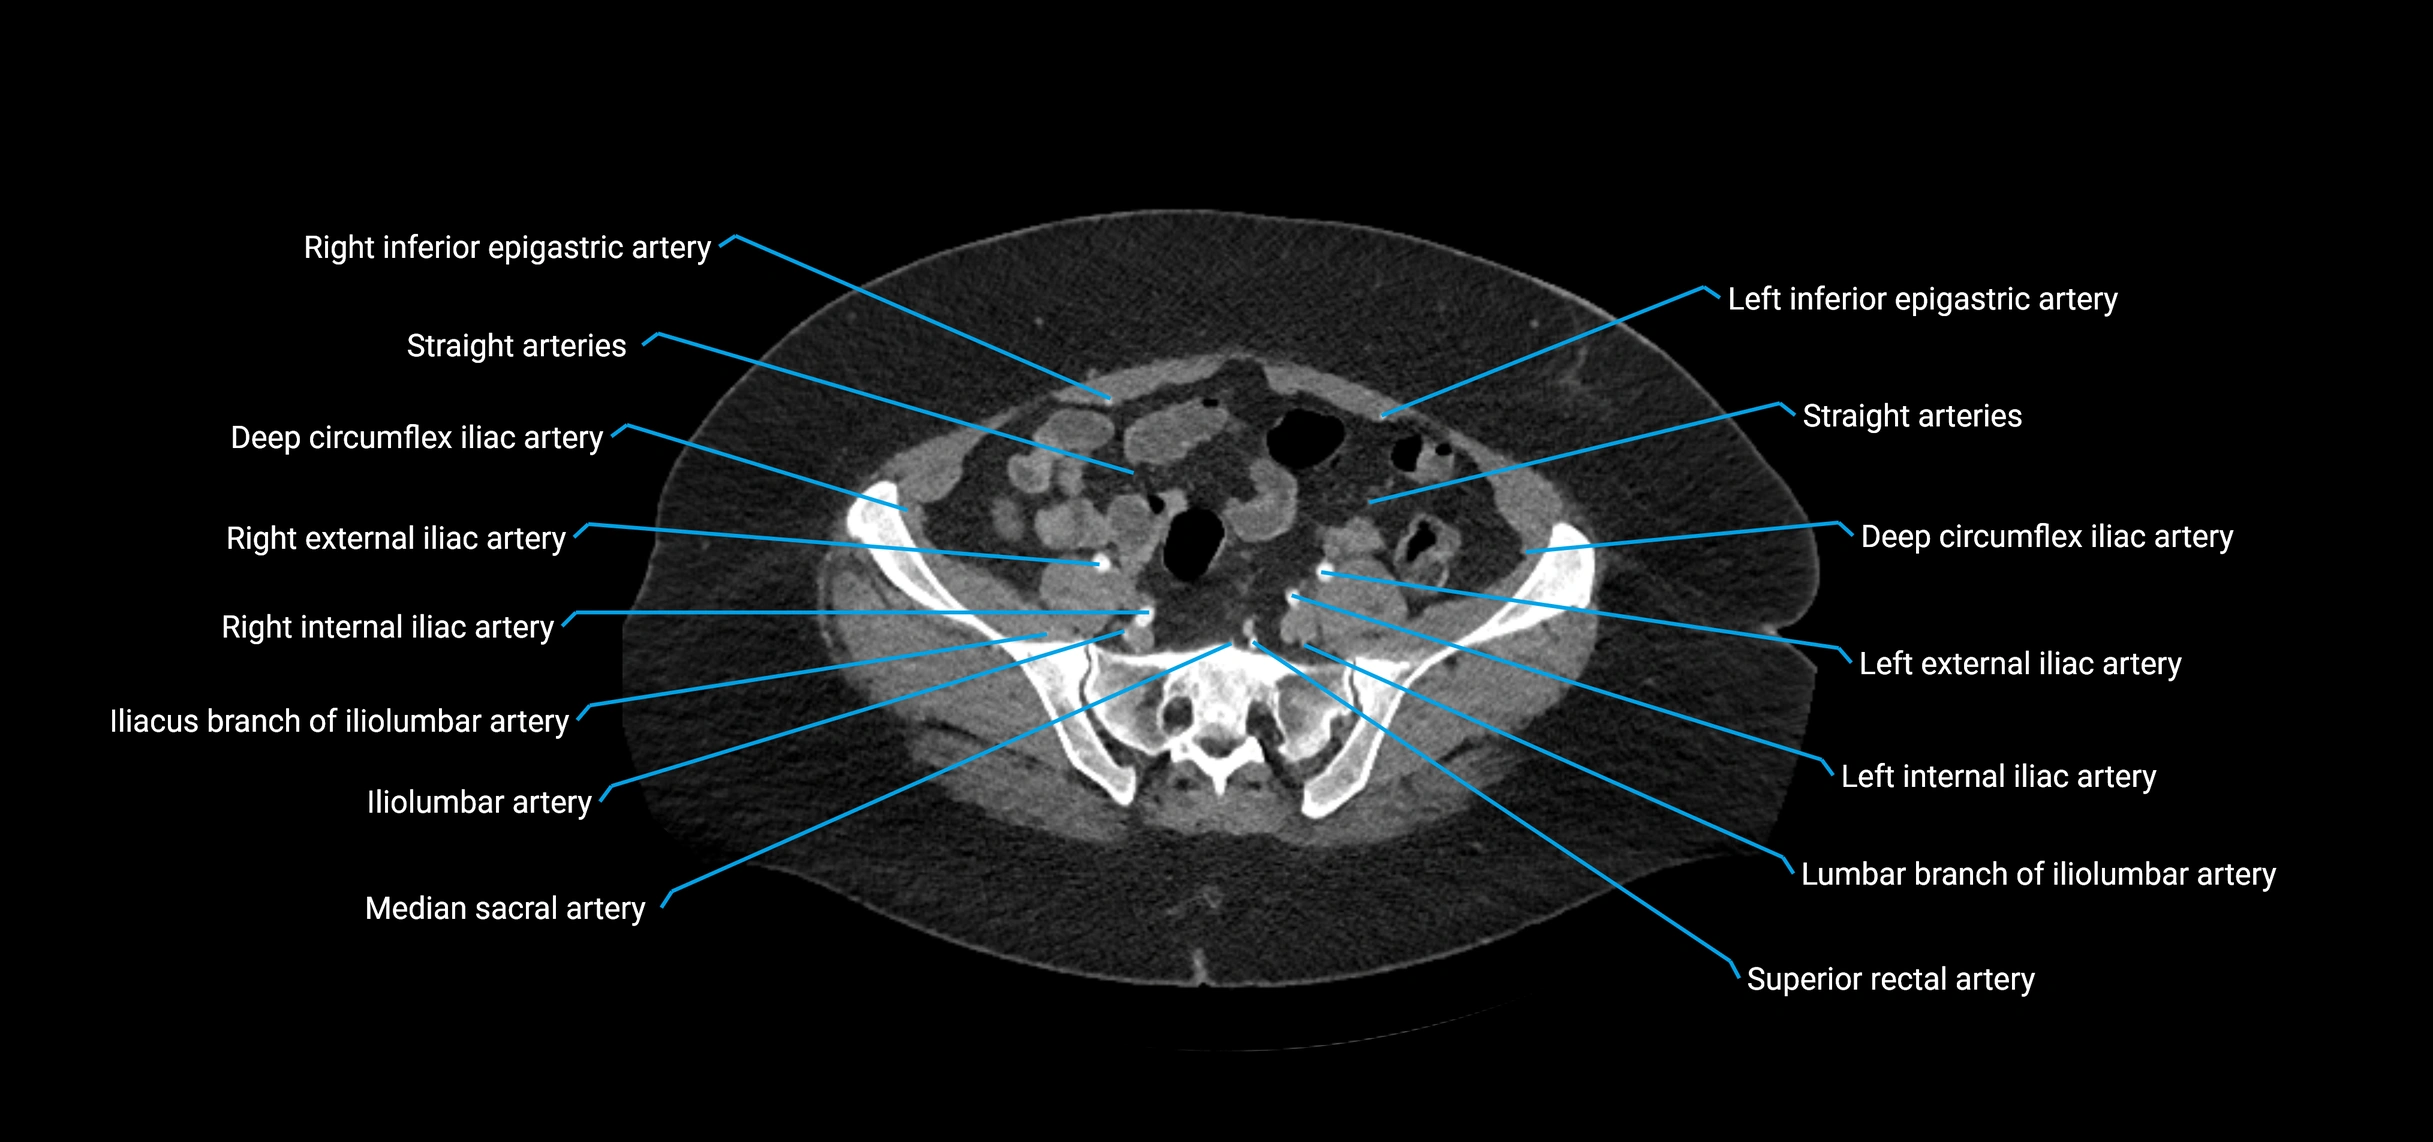

Contrast-enhanced CT (CTA):

• Gold standard for abdominal aortic imaging

• Provides excellent detail of lumen, wall, aneurysm, thrombus, and branch vessels

• Multiplanar and 3D reconstructions help in aneurysm measurement, stent graft planning, and dissection evaluation

• Detects acute rupture, traumatic injury, or occlusion with high sensitivity